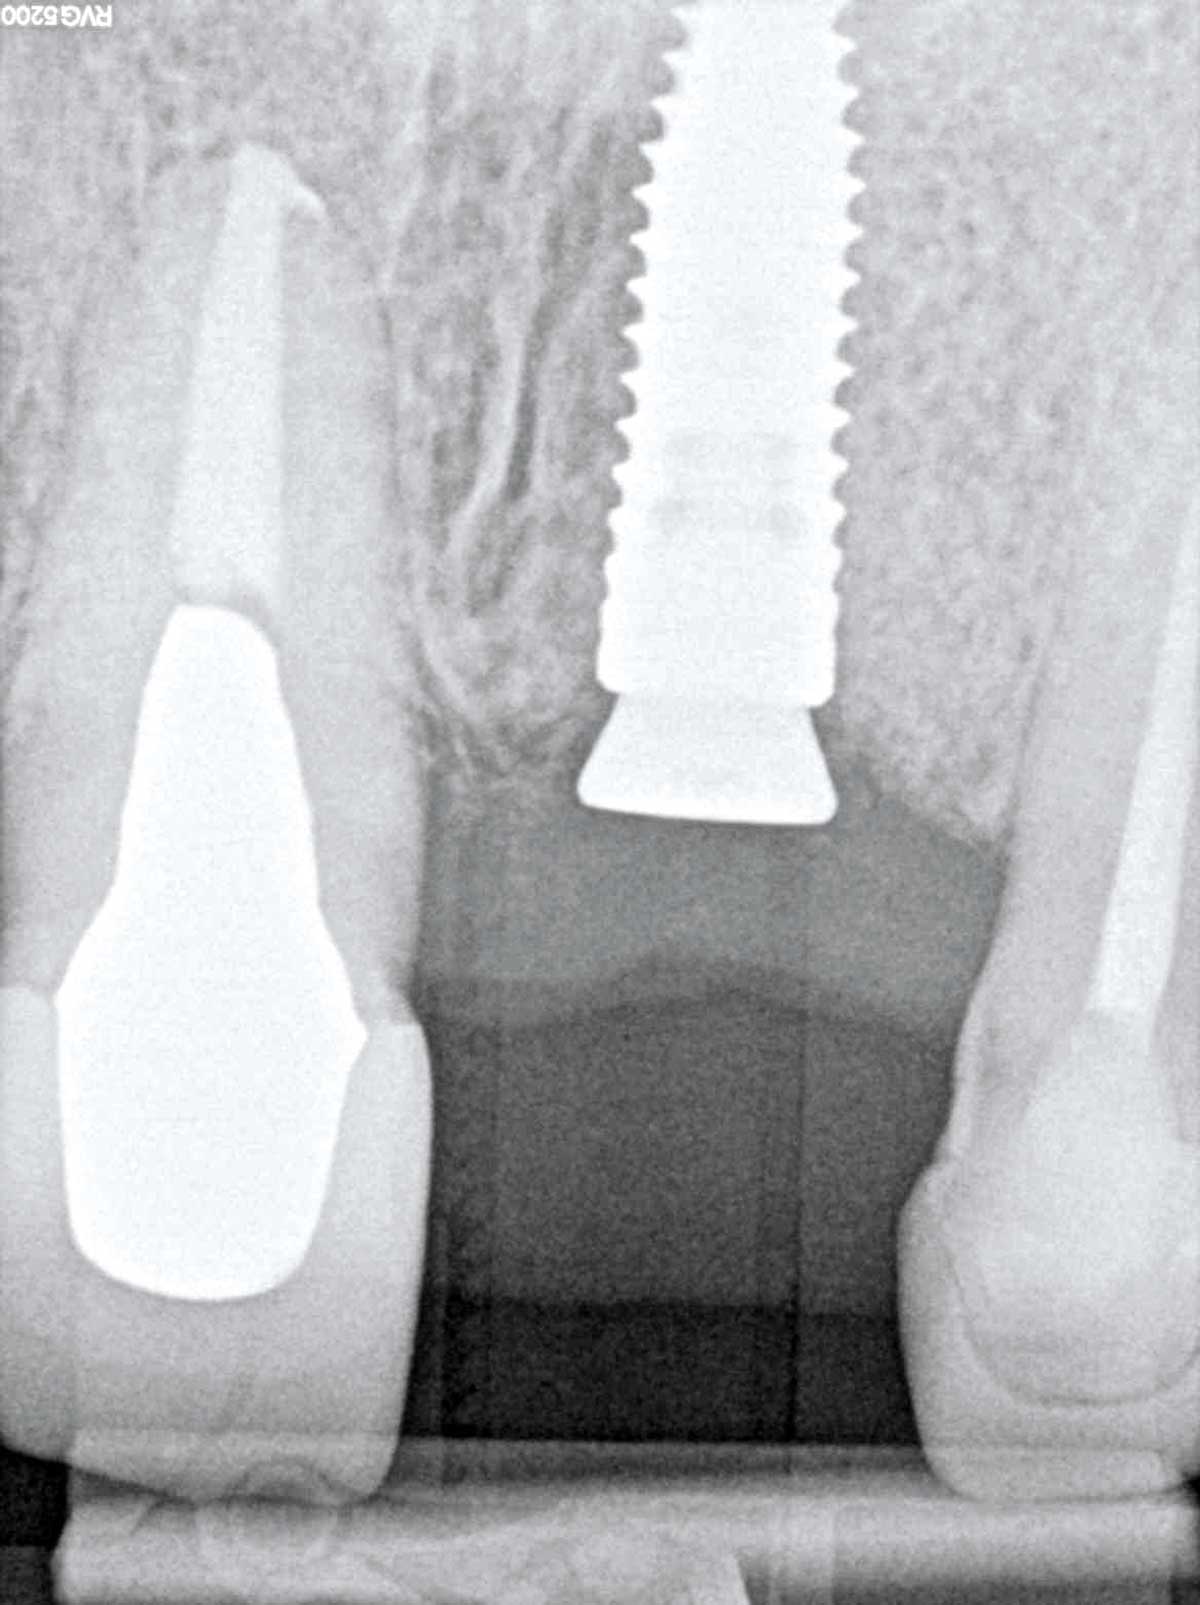

10/10 - Radiographic control after implant placement

Socket augmentation using mucoderm®, maxgraft® and Straumann® Emdogain® - Dr. A. Puišys